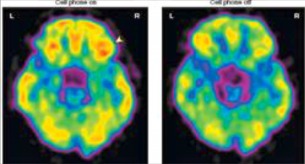

Cette nouvelle étude ne met pas elle non plus à jour de risque accru de cancer. Par contre, elle suggère que les ondes électromagnétiques de radiofréquence émises par les téléphones cellulaires pourraient avoir un impact sur l’activité cérébrale de leurs utilisateurs. Pour arriver à cette observation, une équipe de chercheurs dirigée par le docteur Nora Wolkow du National Institute of Drug Abuse au Maryland a mesuré le métabolisme cérébral du glucose par tomographie à émission de positrons (PET Scan), l’intensité de ce métabolisme étant un bon marqueur de l’activité cérébrale. Pour les besoins de l’étude, qui impliquait 47 individus en bonne santé, un téléphone cellulaire a été placé sur chacune des oreilles des sujets. Deux mesures ont été prises, de 50 minutes chacune. Pour une des mesures, agissant comme contrôle, les deux téléphones, sur l’oreille droite et l’oreille gauche, étaient désactivés. Pour l’autre, le téléphone sur l’oreille droite était activé alors que celui sur l’oreille gauche était complètement désactivé. Le téléphone activé recevait un message enregistré, mais avec le son supprimé pour ne pas causer de stimulation auditive. L’ordre dans lequel ces deux mesures étaient conduites était aléatoire (random) et les participants ne savaient pas à quel ensemble de mesures ils participaient.

L’étude n’a mis en évidence aucune différence globale sur le métabolisme cérébral du glucose. Par contre, les chercheurs ont pu constater une augmentation du métabolisme dans la région du cerveau qui était la plus proche de l’antenne du téléphone activé. Ceci se voit sur la photo de gauche (cf. plus bas), indiqué par une petite flèche. La différence était relativement faible, de l’ordre de 7 %, mais quand même significative. La conclusion des auteurs de l’étude : « … les résultats montrent que chez les humains le cerveau est sensible aux effets des champs électromagnétiques modulés par les radiofréquences provenant de l’utilisation de téléphones cellulaires. »